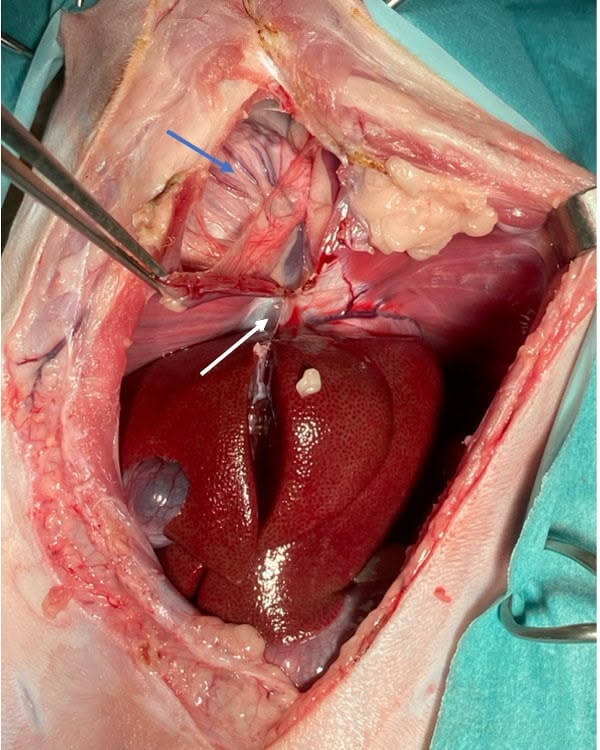

Figure 1

Figure 2